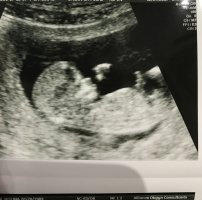

merhaba Ufuk Bey bugün doktora gittim bebeğim 16+2 görünüyor doktor uzun bir süre incelemesine rağmen bacak arasını göremediğini söyledi Ancak doktor bence bu bebek erkek değil erkek olsa şimdiye görürdük dedi .Bacak arasını görmeden böyle bir tahmin yapılır mı ?Aynı doktor 11+4 te açı ölçüp açı 45 derece bu bebek%60 -70 erkek demişti. USG yi size de atmıştım bu konuda bir yorum yaparsanız sevineceğim kafam karıştı. Teşekkürler

Merhaba, usg incelemesi ile cinsiyet tahminin de yanılmalar olabilir. Özellikle 20 haftadan itibaren bebeğin cinsiyeti net olarak gözlemlenebilir. Bacak arası görülmeden tahmin yürütmek yanıltabilir. Yüklemiş olduğunuz görselde nub çıkıntısı görülmüyor bu yüzden sağlıklı bir değerlendirme yapamıyoruz.